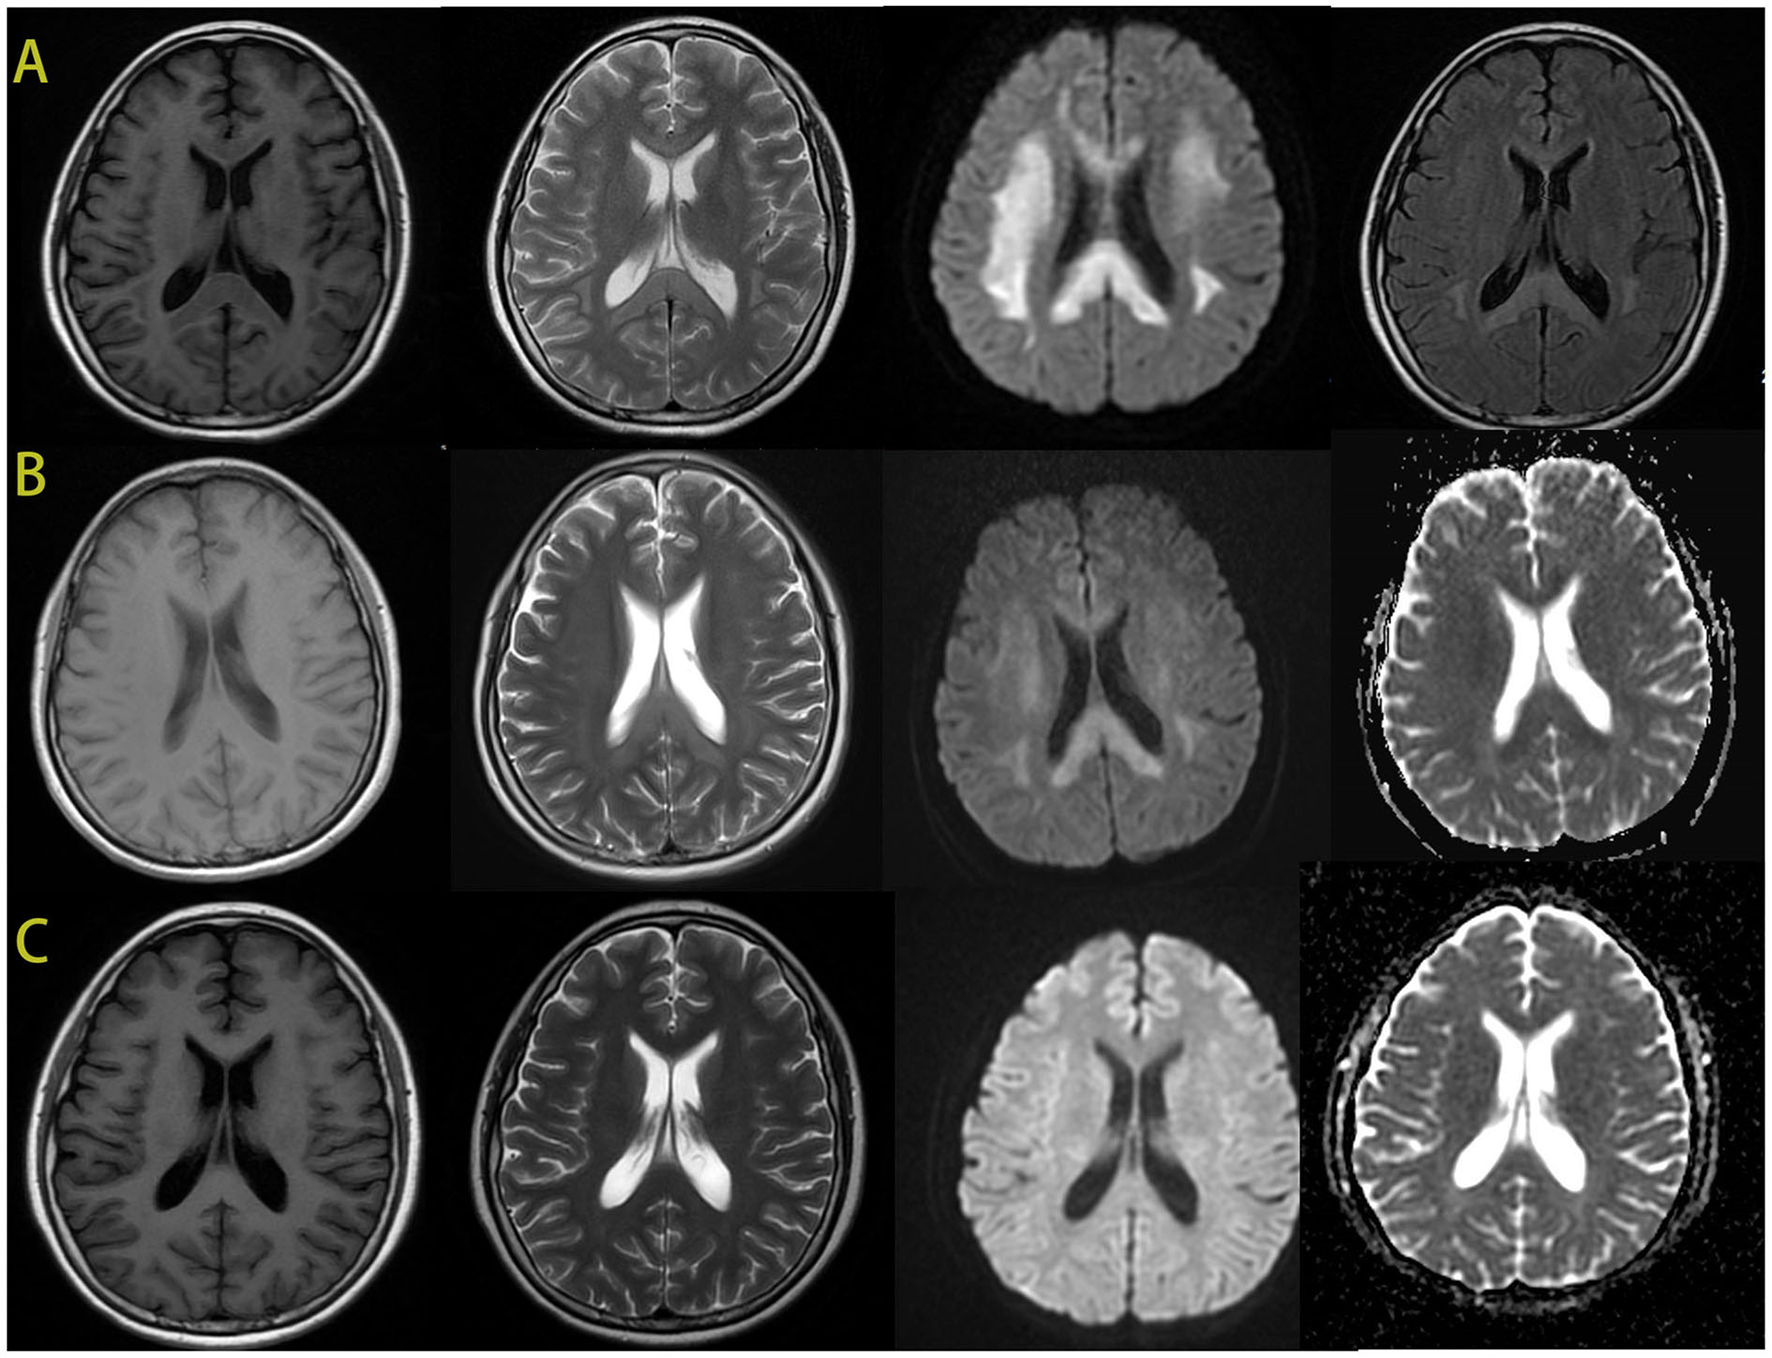

Cerebral MRI showed bilaterally symmetric hyperintensity on DWI signal and abnormal hyperintensity on T2 weight image in the deep white matter and corpus callosum (Figure 2). The abnormal signals gradually reduced and disappeared 4 days later. A month after the encephalopathy, her brain MRI was almost normal (Figure 2). The electroencephalogram (EEG) was normal during the episode.

Figure 2

The brain MRI images of the patient. During the episode, the brain MRI showed hypointense signal in T1-weighted imaging and hyperintensity in T2-weighted imaging in the bilateral deep white matter and the corpus callosum. And there was an obviously bilaterally symmetric hyperintense DWI signal in the same region (A). MRI after 4 days showed improvement of the abnormal signal in white matter, the hypointense ADC signal in the same region (B). After 1 month, the images of her brain were almost normal (C).

Previous studies demonstrated that the pathogenic mechanism of AMB-associated leukoencephalopathy was correlated with the AMB binding to myelin, which led to an increase in membrane permeability and leakage of intracellular components, and eventually resulted in white matter lesion (4). The imaging characteristics of our patient showed hypointense signals on T1-weighted imaging and hyperintensity in T2-weighted imaging in the bilateral deep white matter and the corpus callosum and the hypointense ADC signal in the same region. Based on these characteristics, we also speculated that the pathogenesis might be due to L-AMB binding to myelin and leading to leakage of intracellular components, which then resulted in the cytotoxic edema and white matter lesions. However, the specific pathogenic mechanism needs to be confirmed by more cases.